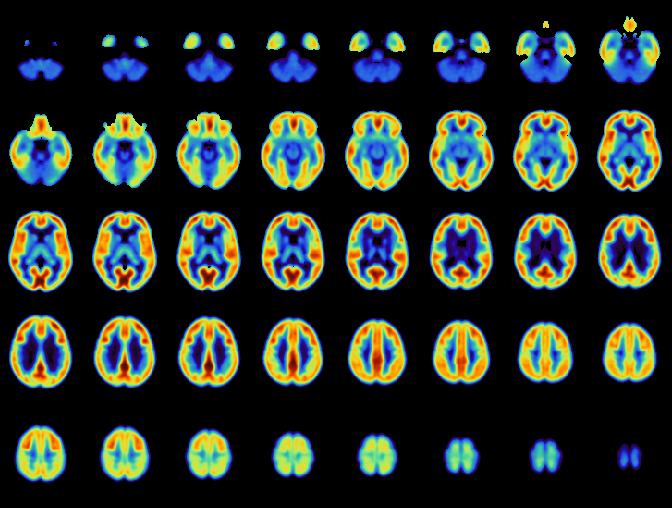

Il team di ricerca ha analizzato un gruppo di 54 persone, 26 con schizofrenia e 28 sane, sottoponendoli a due scansioni PET, Tomografia a Emissione di Positroni, tecnica di diagnostica avanzata per immagini, con un radio-tracciante che si lega selettivamente ai recettori cerebrali della serotonina. Tra le due scansioni le persone hanno ricevuto una singola dose di d-amfetamina, inducendo indirettamente il rilascio di serotonina. L’osservazione ha evidenziato un rilascio di serotonina molto più marcato nella corteccia frontale e, in particolare, nei soggetti con schizofrenia rispetto al gruppo di controllo. Ulteriori analisi hanno stabilito un legame diretto tra questo picco, la severità dei sintomi negativi e il grado di disabilità funzionale. "I dati sono stati raccolti tra il 2015 e il 2024 - si legge nello studio -. Hanno partecipato pazienti ambulatoriali adulti stabili con schizofrenia secondo il DSM-5 (manuale di riferimento globale per la psichiatria, ndr), senza antipsicotici o in terapia con antipsicotici con affinità trascurabile per i recettori 5-HT2A del recettore 2A della 5-idrossitriptamina, e soggetti sani abbinati per età, sesso e indice di massa corporea".

Lucia Maccioni analizza il risultato: "Quando c'è un rilascio di serotonina, indotto dallo stimolo, il tracciante trova meno recettori liberi a cui legarsi. Noi quantifichiamo questa diminuzione del legame (binding) attraverso modelli compartimentali. Abbiamo visto che i due gruppi rispondono in modo differente: il rilascio di serotonina è maggiore nei pazienti con schizofrenia. L'aspetto più interessante è che l’aumento è legato ai sintomi della patologia: queste disregolazioni rappresentano target plausibili su cui agire per ridurre i sintomi".

"Lo studio è stato possibile grazie alla PET. In questo ambito Padova è un'eccellenza perché, per analizzare queste immagini, servono ingegneri e modelli matematici - continua Veronese -. È su questo punto che abbiamo lavorato: per interpretare l'immagine servono analisi numeriche. Nello specifico, abbiamo usato un tracciante chiamato CIMBI-36, sensibile alle variazioni di serotonina. La chiave è questa: non misuriamo la serotonina 'di base', ma il suo rilascio indotto da una stimolazione dopaminergica. La complessità sta proprio nel misurare il rilascio di un neurotrasmettitore attraverso la stimolazione di un altro. Abbiamo quantificato questo rilascio sia nei soggetti sani che nei pazienti, ricavandone le statistiche alla base dello studio".